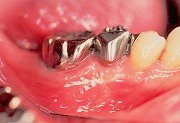

7

| 術後1週目。この時期までは患者によるプラークコントロールは一切行わせず、週2~3回来院させて、術者によるプラークコントロールを行う。 |

8

| 術後3週目。術後1週目より縫合糸を順次除去していく。歯肉が安定した状態になるまで懸垂縫合のみを残しておく。患者によるプラークコントロールが完全に行われているのがわかる。 |